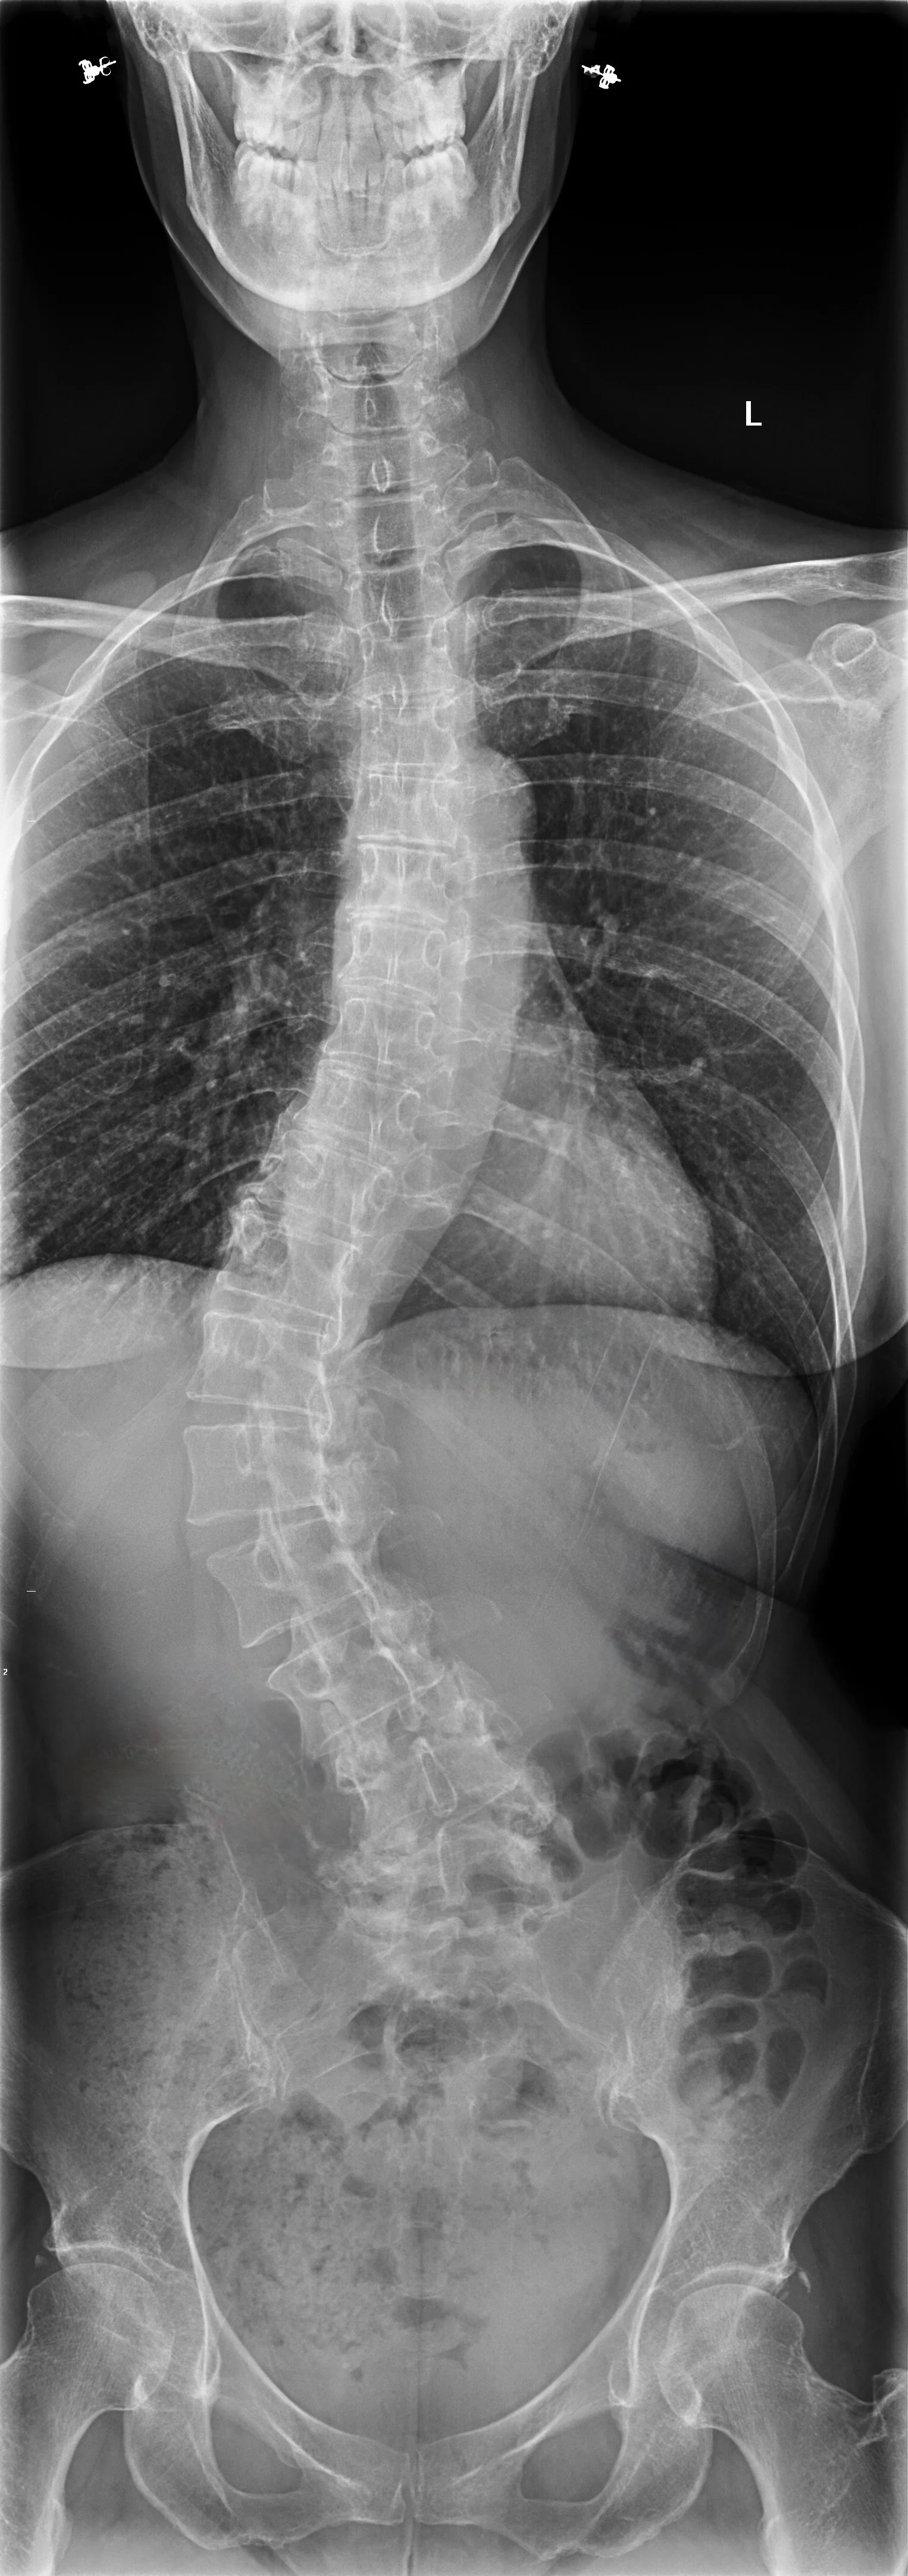

Why I Care About Scoliosis

By Theresa Shay

Me, age 56

Forty-six years since diagnosis